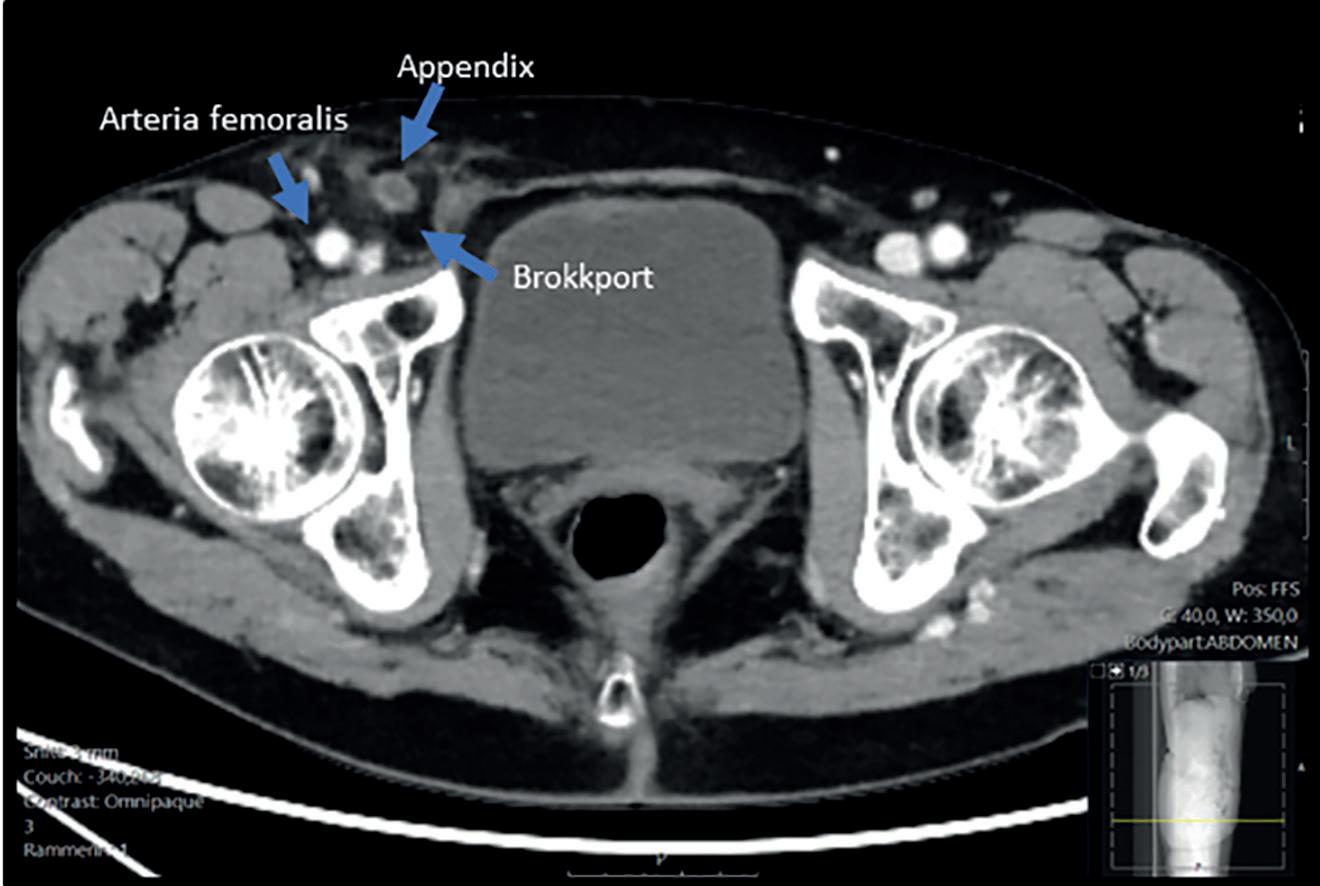

Du er på din femte måned som LIS i kirurgi på et lite lokalsykehus. Du har nettopp kommet på nattevakt og er på vei til akuttmottaket for å tilse flere pasienter som ligger og venter. En 21 år gammel mann er meldt inn med perianal abscess, og på vei inn til ham går du gjennom din mentale sjekkliste før oppmelding til kirurgi. Når du undersøker pasienten mistenker du at han har en abscess, men den sitter ikke der du forventet. Pasientens hud er rød og irritert i midtlinjen mellom nates og har tre små åpninger hvor det tømmer seg blodig, blakket væske. Til venstre for midtlinjen er det en øm, fluktuerende oppfylning på ca. 3 x 3 cm som ligger 10 cm kranialt for endetarmsåpningen. Pasienten er ved god allmenntilstand. Han er afebril, har leukocytter innenfor referanseområdet og CRP 14. På listen din over differensialdiagnoser har du kanskje perianal abscess, hidradenitis suppurativa og pilonidal abscess. Disse tilstandene bør gjenkjennes og diagnostiseres klinisk.

«Kjært barn har mange navn», sies det. Pilonidal sinus, «tvilling» og sakralcyste er begreper som gjerne brukes om hverandre når det snakkes om pilonidal sykdom. Denne artikkelen omhandler sykdomstilstanden som befinner seg i midtlinjen, nærmere bestemt glutealkløften, eller rima internates (rumpesprekken) om du vil. For ordens skyld nevnes det at tilstanden også kan finnes i eksempelvis navlen, hodebunn og mellom fingrene. Insidensen av pilonidal sykdom estimeres til 26 per 100.000 innbyggere (1). Tilstanden er ervervet og debuterer oftest i 20-årsalderen. Den ses sjelden etter fylte 40 år. Begge kjønn affiseres, menn to til tre ganger hyppigere

enn kvinner. Risikofaktorer er overvekt, lokalt traume, dyp glutealkløft, hirsutisme, stillesittende livsstil og polycystisk ovariesyndrom (PCOS)(1-3). Tilstanden kan debutere uten at noen av de ovennevnte risikofaktorer er til stede.